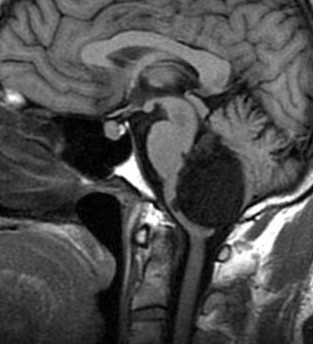

![эпенд 4-саг]()

![эпенд 4-акс-Т2]()

МРТ головного мозга. Эпендимома IV желудочка. Сагиттальная Т1-зависимая МРТ, аксиальные Т2-зависимая МРТ и МРТ типа FLAIR.